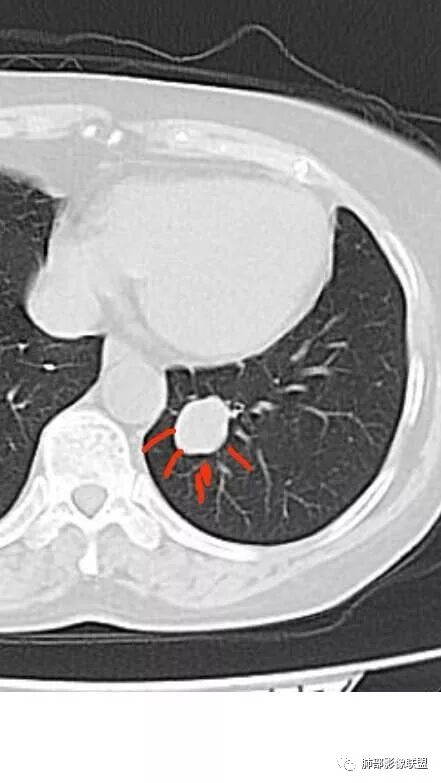

横断位应该显示了这个支气管,当时记得特意考下来图了

M-Imaging :周围有黑边,错构呢?南边:如果明确没堵塞就好办这个最主要的就是这个支气管是否堵塞没堵塞,支持PSP杨泽锋:如果是气管腔内起源的那就要考虑类癌M-Imaging :不见明显冰山征,没有钙化南边:心里不是很踏实,就是没看到支气管全景Forever:强化如果不高 我还是考虑小细胞肺癌或者腺癌

崔刚:有个层面支气管在病灶周边Yiren  Sishui(厶水伊人):其实就是PSP与类癌的鉴别M-Imaging :Forever:如果分不清结构关系了 这个时候强化还是有很大参考价值M-Imaging :周围有黑边崔刚:没有钙化和脂肪,张老师是不是考虑错构瘤?徐超:黑边是想说错构瘤M-Imaging :是啊滴水海:psp也可Forever:不像 觉得ct值有点高。一般错构瘤ct值低于20,没有钙化

滴水海:有黑晕更支持pspM-Imaging :黑边代表局限肺气肿错构瘤,应该和血管没有关系,这例血管贴近毛勤香:考虑PSP或错构瘤,类癌代排南边:我的判断原则:支气管无关——良性、间叶来源良性,强化明显——PSP,尤为明显——糖瘤,不明显——错构瘤

1.图片未能提供病灶与支气管的确切关系,支气管截断有助于大细胞癌或腺癌的判断,管腔狭窄有助于小细胞癌的判断。